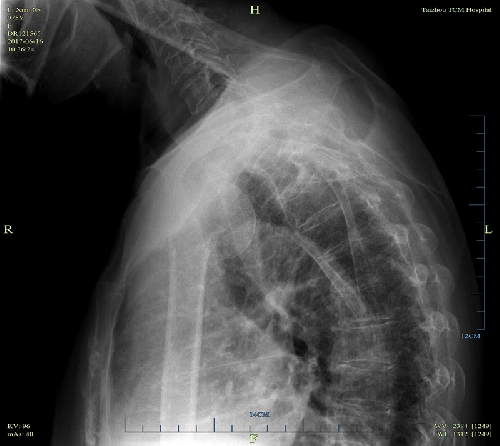

近日,我院骨三科獨(dú)立完成了首例 “人工肱骨頭置換術(shù)”?;颊呃頧X,女,75歲,因摔傷致右肩腫痛、活動(dòng)不利4小時(shí)入院。查體判斷:右肩部無(wú)腫脹,局部壓痛,縱向叩擊痛陽(yáng)性,右肩上舉、外展受限,肢端血循、感覺(jué)良好。X片示:右肱骨近端粉碎性骨折,移位明顯。CT示:右肱骨上端骨質(zhì)斷裂,呈粉碎性,大、小結(jié)節(jié)骨折,斷端位置差,關(guān)節(jié)在位。診斷為:右肱骨近端粉碎性骨折(四部分骨折)。為了緩解患者疼痛,改善肩關(guān)節(jié)功能,提高生活自理能力,經(jīng)科室討論決定,對(duì)于高齡肱骨近端粉碎性四部分骨折,應(yīng)采用人工肱骨頭置換術(shù)。

術(shù)前X片正位 術(shù)前X片穿胸位